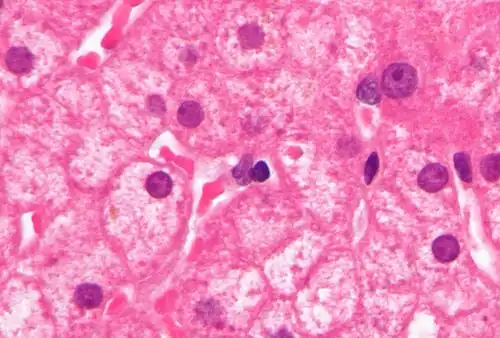

Lipofuscin is the name given to fine yellow-brown pigment granules composed of lipid-containing residues of lysosomal digestion.[1][2] It is considered to be one of the aging or "wear-and-tear" pigments, found in the liver, kidney, heart muscle, retina, adrenals, nerve cells, and ganglion cells.[3]

Lipofuscin appears to be the product of the oxidation of unsaturated fatty acids and may be symptomatic of membrane damage, or damage to mitochondria and lysosomes. Aside from a large lipid content, lipofuscin is known to contain sugars and metals, including mercury, aluminium, iron, copper and zinc.[4] Lipofuscin is also accepted as consisting of oxidized proteins (30–70%) as well as lipids (20–50%).[5] It is a type of lipochrome[6] and is specifically arranged around the nucleus.

Lipofuscin accumulation in the eye is a major risk factor implicated in macular degeneration, a degenerative disease,[15] and Stargardt disease, an inherited juvenile form of macular degeneration.

Also, pathological accumulation of lipofuscin is implicated in Alzheimer's disease, Parkinson's disease, amyotrophic lateral sclerosis, certain lysosomal diseases, acromegaly, denervation atrophy, lipid myopathy, chronic obstructive pulmonary disease,[16] and centronuclear myopathy. Accumulation of lipofuscin in the colon is the cause of the condition melanosis coli.